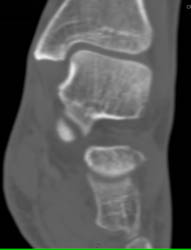

Osteoid Osteoma With Bone Remodelling